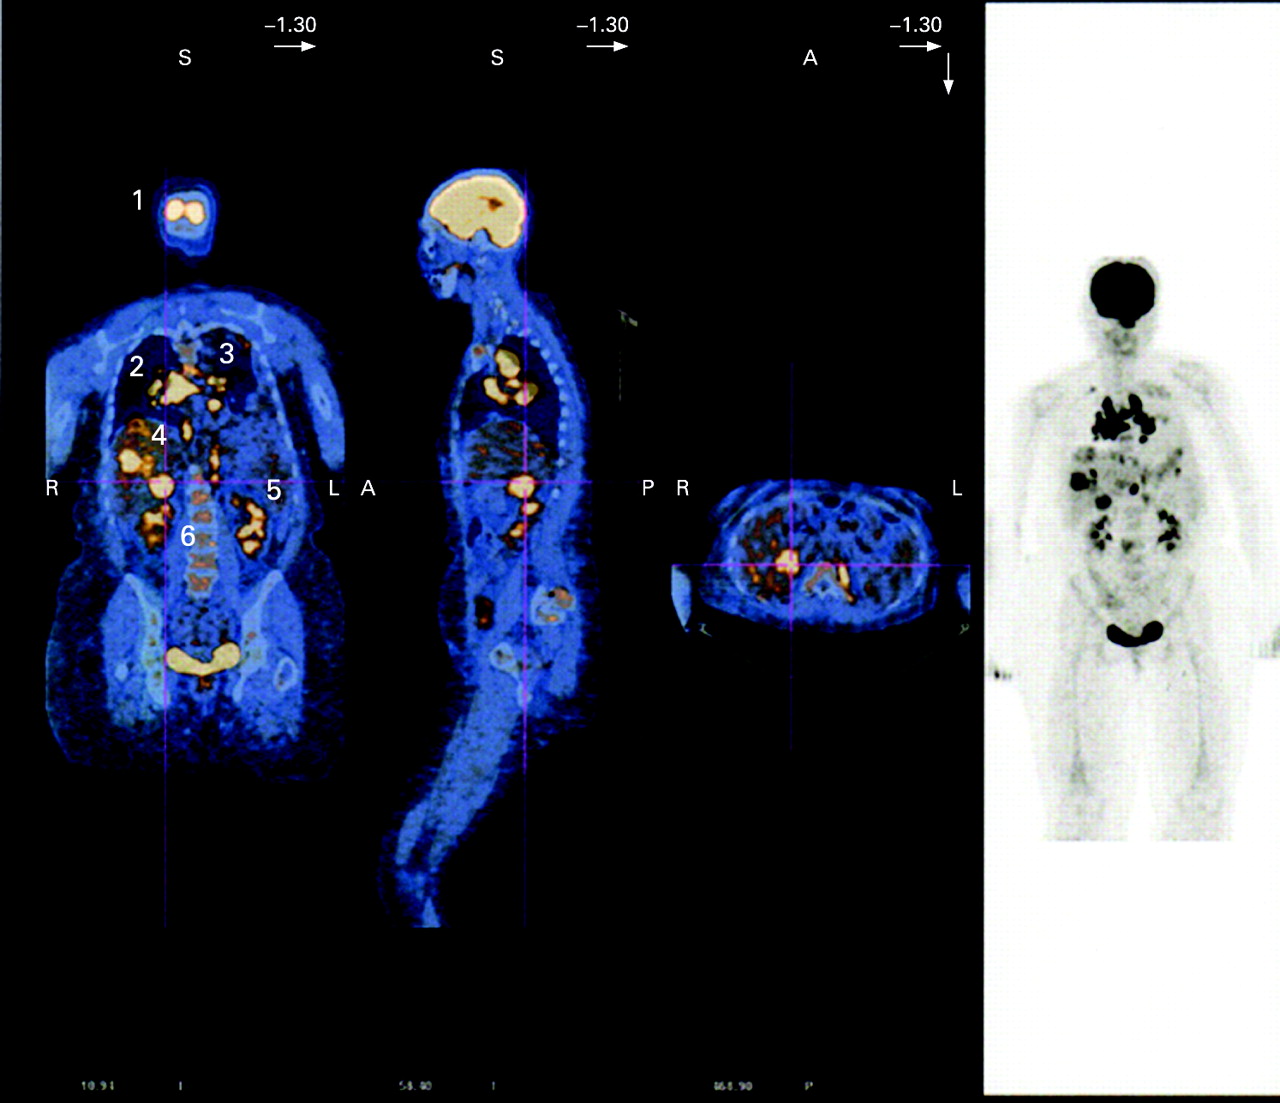

Facilitate learning with our scientific Pet/ct Lymphatic System gallery of hundreds of educational images. accurately representing photography, images, and pictures. perfect for research publications and studies. Browse our premium Pet/ct Lymphatic System gallery featuring professionally curated photographs. Suitable for various applications including web design, social media, personal projects, and digital content creation All Pet/ct Lymphatic System images are available in high resolution with professional-grade quality, optimized for both digital and print applications, and include comprehensive metadata for easy organization and usage. Explore the versatility of our Pet/ct Lymphatic System collection for various creative and professional projects. Multiple resolution options ensure optimal performance across different platforms and applications. Whether for commercial projects or personal use, our Pet/ct Lymphatic System collection delivers consistent excellence. Professional licensing options accommodate both commercial and educational usage requirements. Each image in our Pet/ct Lymphatic System gallery undergoes rigorous quality assessment before inclusion. Time-saving browsing features help users locate ideal Pet/ct Lymphatic System images quickly. Advanced search capabilities make finding the perfect Pet/ct Lymphatic System image effortless and efficient. Comprehensive tagging systems facilitate quick discovery of relevant Pet/ct Lymphatic System content. Instant download capabilities enable immediate access to chosen Pet/ct Lymphatic System images.